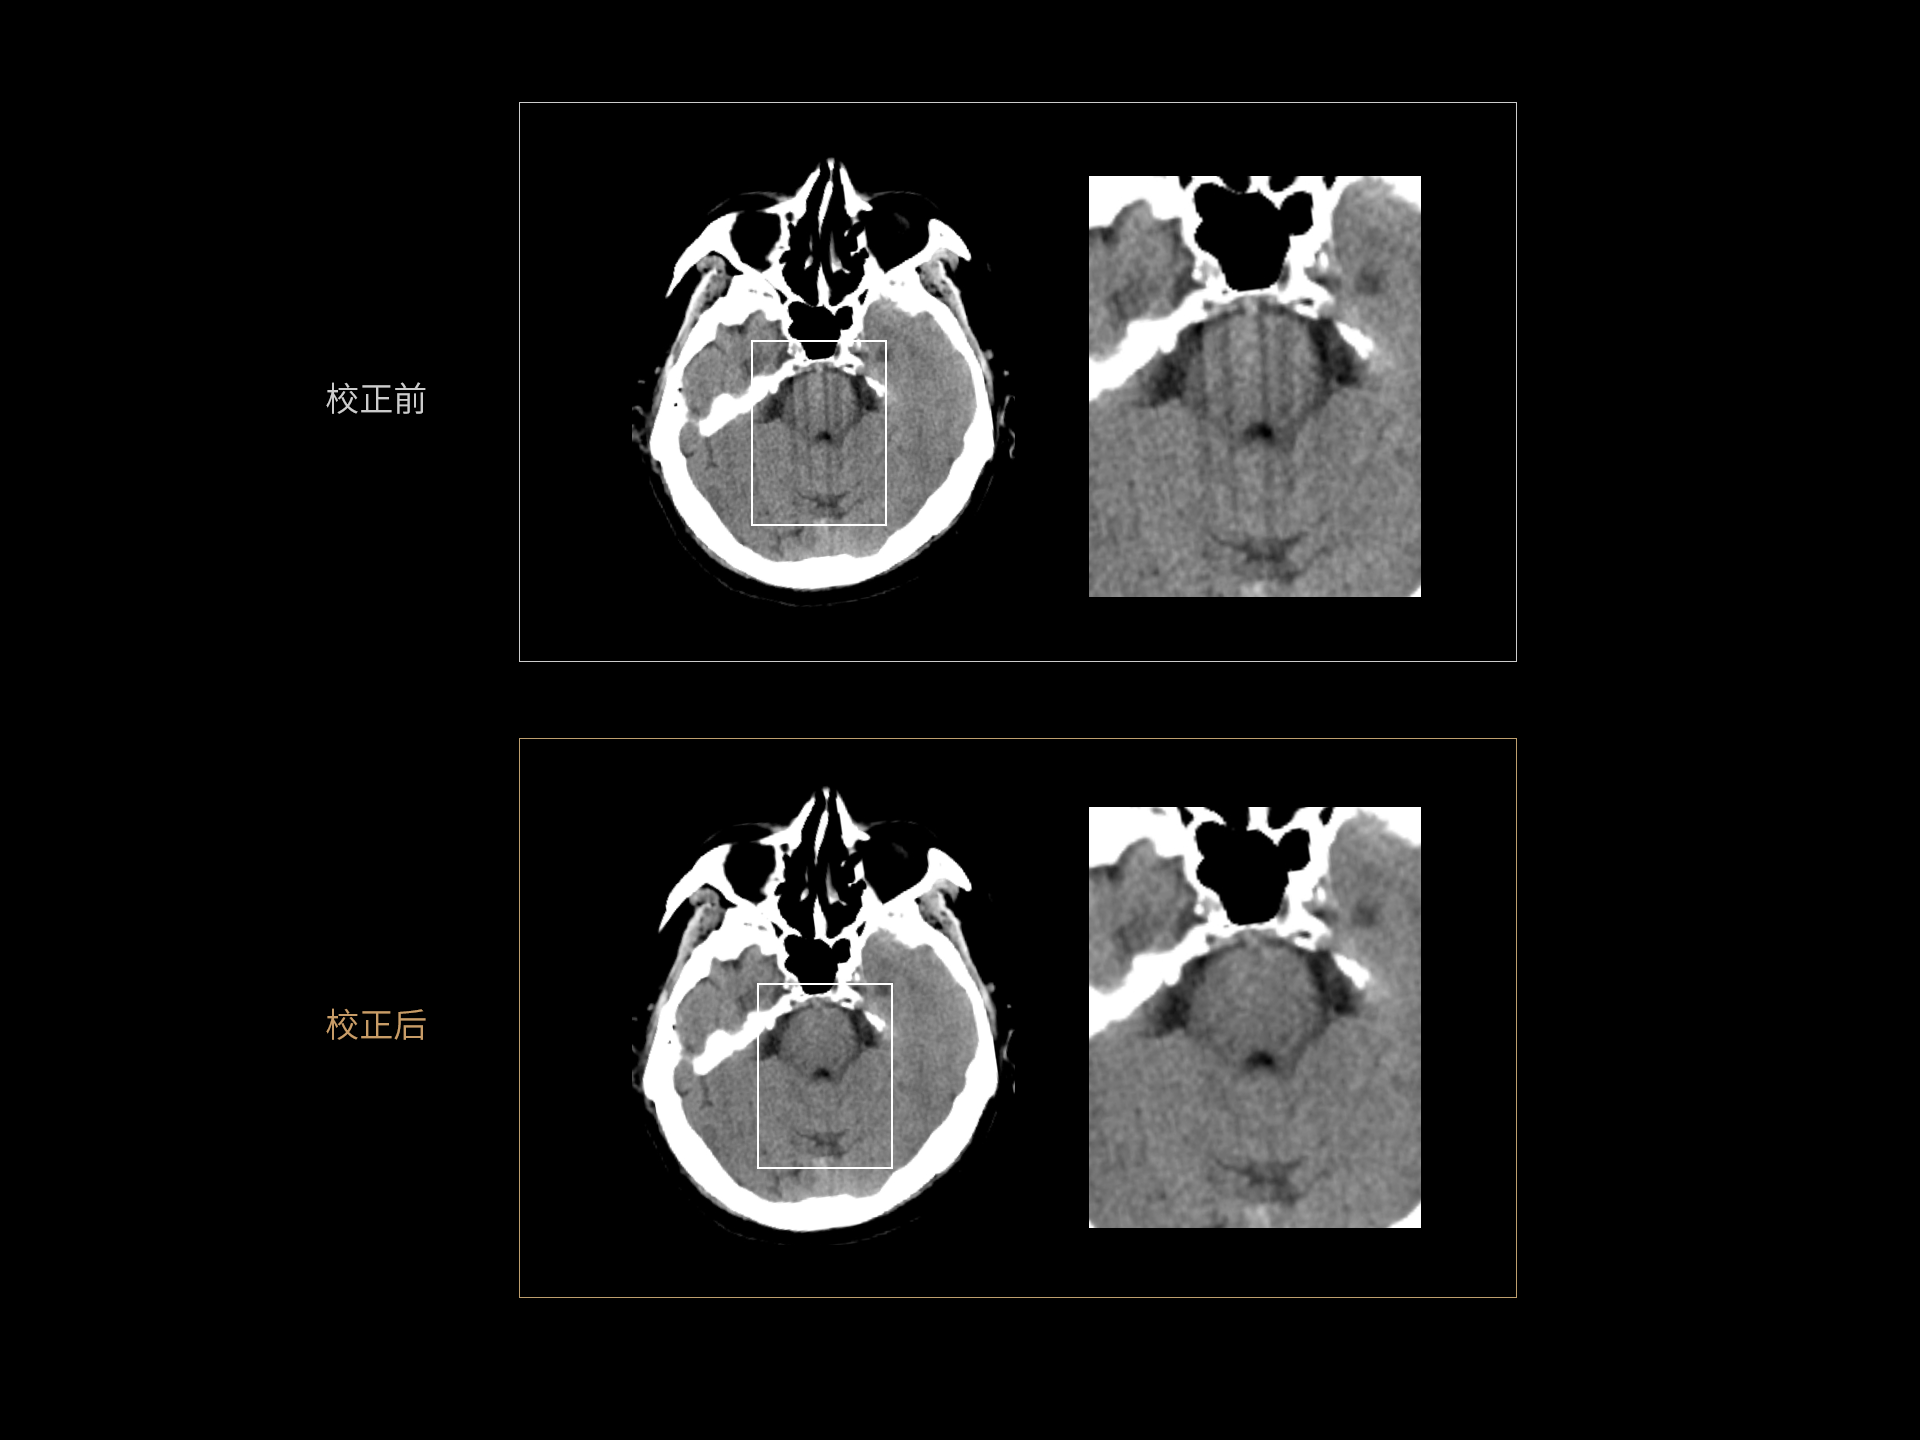

Motion Freeze技术:基于深度学习技术校正头部运动伪影,保持头部结构清晰显示。